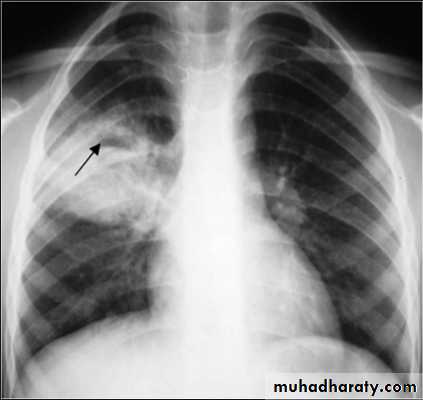

Nodular (coin) lesion in the left upper lung with irregular edge (most probably cancinoma